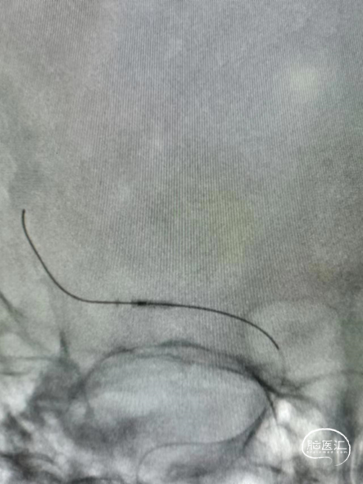

Guiding到位,导丝通过病变。

球囊通过病变。